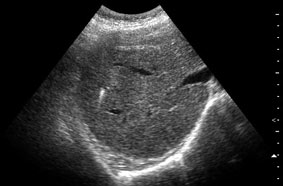

Привожу еще один пример.

Женщина 70 лет,15 лет назад проведена холецистэктомия. Жалобы на боли в эпигастрии.

Наиболее вероятные варианты: хронический холангит, мелкие конкременты внутрипеченочных желчных протоков, холестероз.

на некоторый картинках - действительно - мелкие конкременты желчных ходов,

на других - просто перифокальные изменения стенок сосудов.